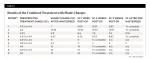

Upon completion of the established case study protocol, the nine subjects demonstrated an average change of 11.1 shades (Table 1). The patient with the least shade change still demonstrated an improvement of 5 shades, and the patient with the next lowest shade change demonstrated a change of 8.83 shades. Two subjects achieved a maximum change of 14 shades.